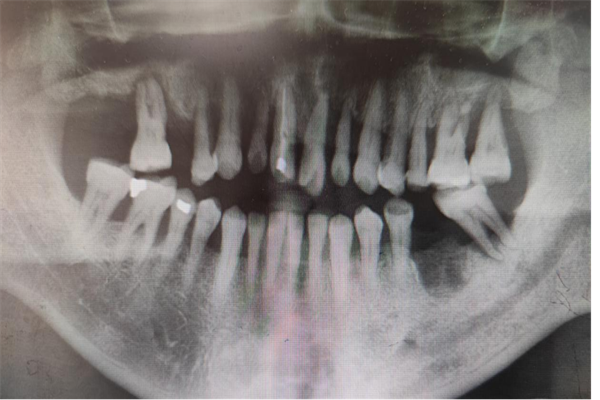

術前曲面斷層片檢查

接診后,王可醫(yī)生認真聽取了李伯的訴求,并與楊濤主任一同對李伯的病情進行了分析討論。經(jīng)過與家屬充分溝通并征得同意后,決定對李伯實施拔除松動牙后即刻行數(shù)字化全口種植牙術,術后即刻行過渡義齒修復,降低等待期間缺牙對美觀及咀嚼功能的影響。